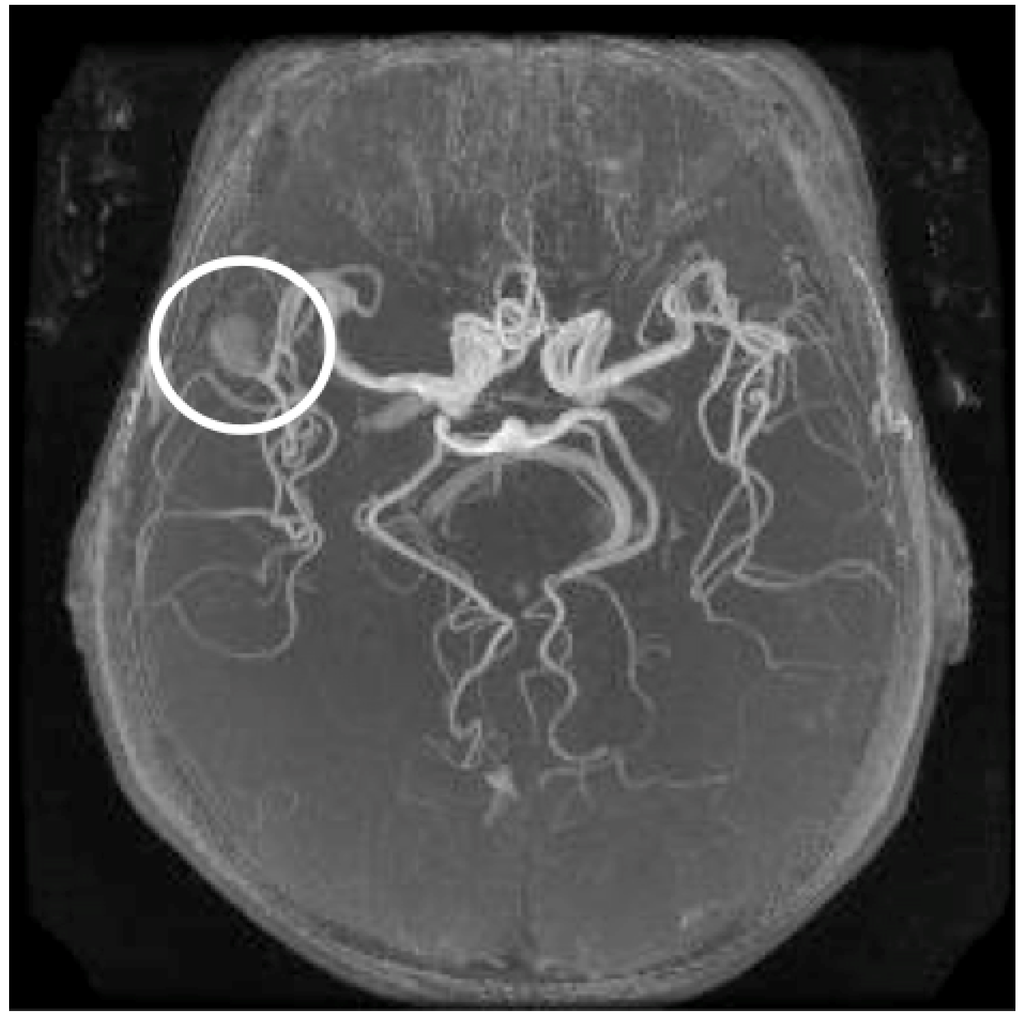

In recent years, various kinds of CAD methods have been developed in the neuroradiology using MR images [25,26,27,28,29,30,31]. Radiologists expect that CAD systems can improve their diagnostic abilities based on synergistic effects between the computer’s and radiologist’s high abilities by using the information analysis including the medical images. For instance, Figure 1 shows an illustration of the output by a CAD system for detection of intracranial aneurysms in MR angiography (MRA) images. In this review paper, we describe the basics and the recent researches of CAD systems for brain diseases in the field of neuroradiology. In Section 2, the fundamental techniques used for CAD systems for neuroradiology are explained, including image processing and pattern recognition. Several application examples of CAD approaches are introduced in Section 3, including detection of abnormalities, e.g., aneurysms in MRA images, white matter hyperintensities (ischemic lesions and lacunar infarction), Alzheimer’s disease, MS lesions, and classification of brain tumors in MR images. In Section 4, we conclude with possibilities in the future of CAD systems.

Figure 1.

An illustration of the output by a CAD system for detection of intracranial aneurysms in MRA images [25,26].